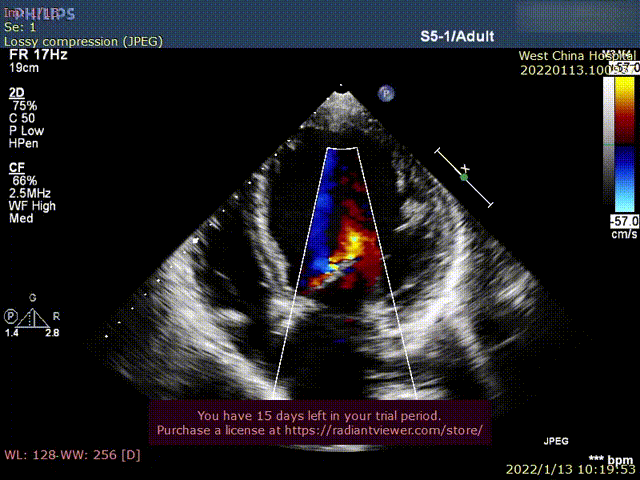

患者为69岁男性,因“活动后胸闷,气紧十年余,加重1月”主诉入院。术前超声提示:左心明显增大,LVDD 82mm,LVEF 26%,主动脉瓣重度狭窄伴重度反流。术后即刻主动脉瓣大量反流消失,超声显示LVDD 65mm,左心较术前显著缩小。

术前超声影像